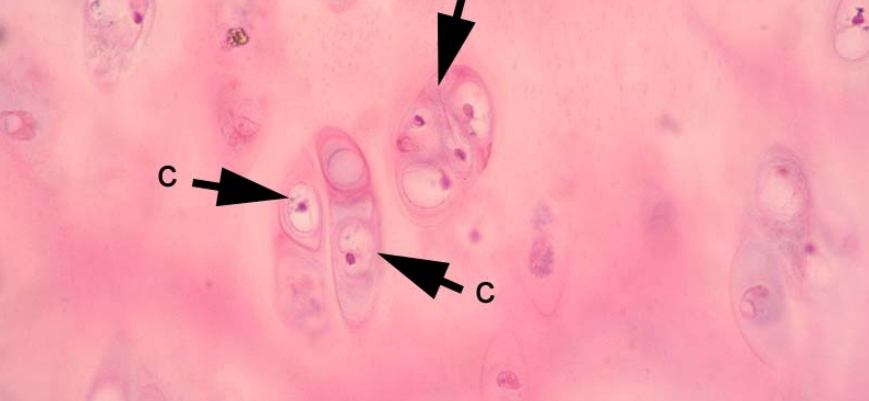

what is this cell?

what is its function?

what percentage of epidermal cells is it

langerhan cell with a cell process

Antigen presenting cells from bone marrow

z 2-8% of epidermal cells

z One component of SALT

z Unique organelle in TEM - Birbeck granule